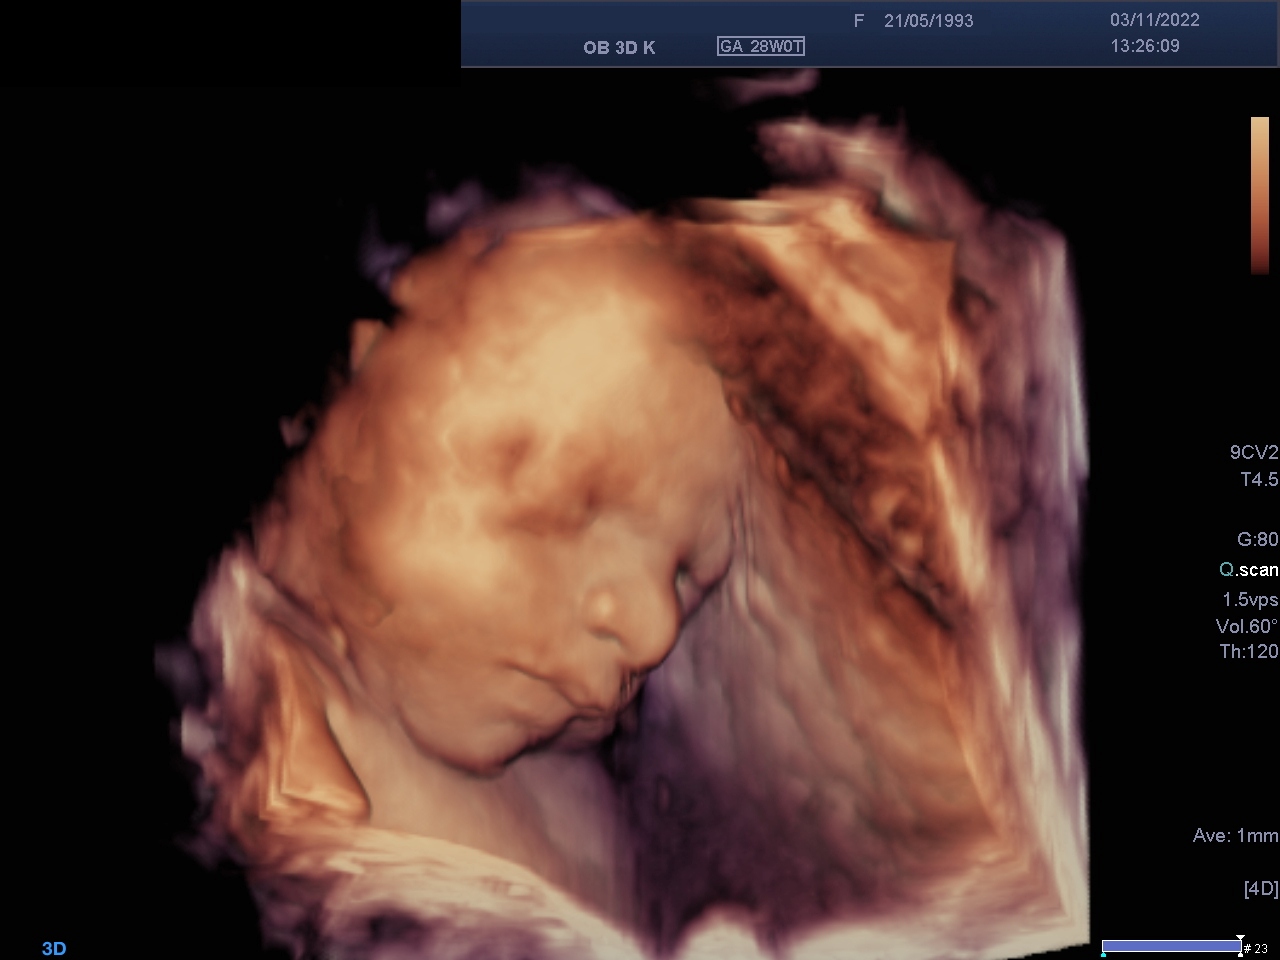

3D-/ 4D- Sonographie

Bei der 3D-Sonographie werden die normalen 2D- Schnittebenen des Ultraschalls in einem Volumenblock zusammengefasst, ähnlich der Computertomographie. Ermöglicht wird dies i.d.R. durch spezielle Schallköpfe, die in der Lage sind, Ultraschallebenen mit definierten Abständen direkt hintereinander abzutasten. Danach ist es möglich, neue Schnittebenen aus diesem Volumenblock zu rekonstruieren, die aber nicht an die Qualität der Originalebenen heranreichen. Neben anderer Darstellungsmöglichkeiten ist besonders das Oberflächenrendering bekannt, in dem vor allem das fetale Profil eindrucksvoll dargestellt werden kann.

Die 4D-Sonographie ist eine zeitliche Abfolge von 3D- Volumen; es wird also ein kurzer Film in Echtzeit aufgenommen.

Die 3D-Sonographie ermöglicht die plastische Darstellung des Feten.